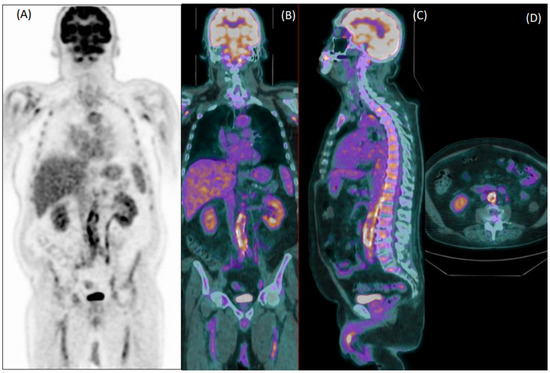

Collectively, 22/76 patients wrongly classified by reader 1 and 22/92 patients misclassified by reader 2 were elderly overweight patients who were taking steroids at the time of imaging. Figure 3 shows an example of a false negative PET exam during corticosteroid treatment.

Figure 3. Coronal [18F]FDG PET (A) and fused PET/CT coronal (B), sagittal (C), and axial (D) images of a 60-year-old female patient with giant cell arteritis, who performed the exam in the course of corticosteroid therapy. Both readers evaluated images as negative for arteritis.